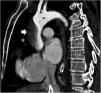

A patient is admitted to the hospital for an acute coronary syndrome complicated by a ventricular septal defect (VSD). Initially, treatment was performed with primary angioplasty and surgical correction of the VSD. During the procedure, the patient developed cardiogenic shock, requiring an intra-aortic balloon pump and a VA-ECMO. The VSD persisted despite treatment, leading to a heart transplant recommendation at a referral center. Prior to this, a CTA (computed tomography angiography) revealed an image consistent with an ascending aortic dissection (Images 1 and 2), resulting in the transplant being deferred. After reviewing the images at the transplant center, the aortic dissection was ruled out following assessment by transesophageal echocardiography of the aortic arch (Image 3), determining that the image was due to the confluence of ECMO flows, which eventually allowed the transplant to be performed.